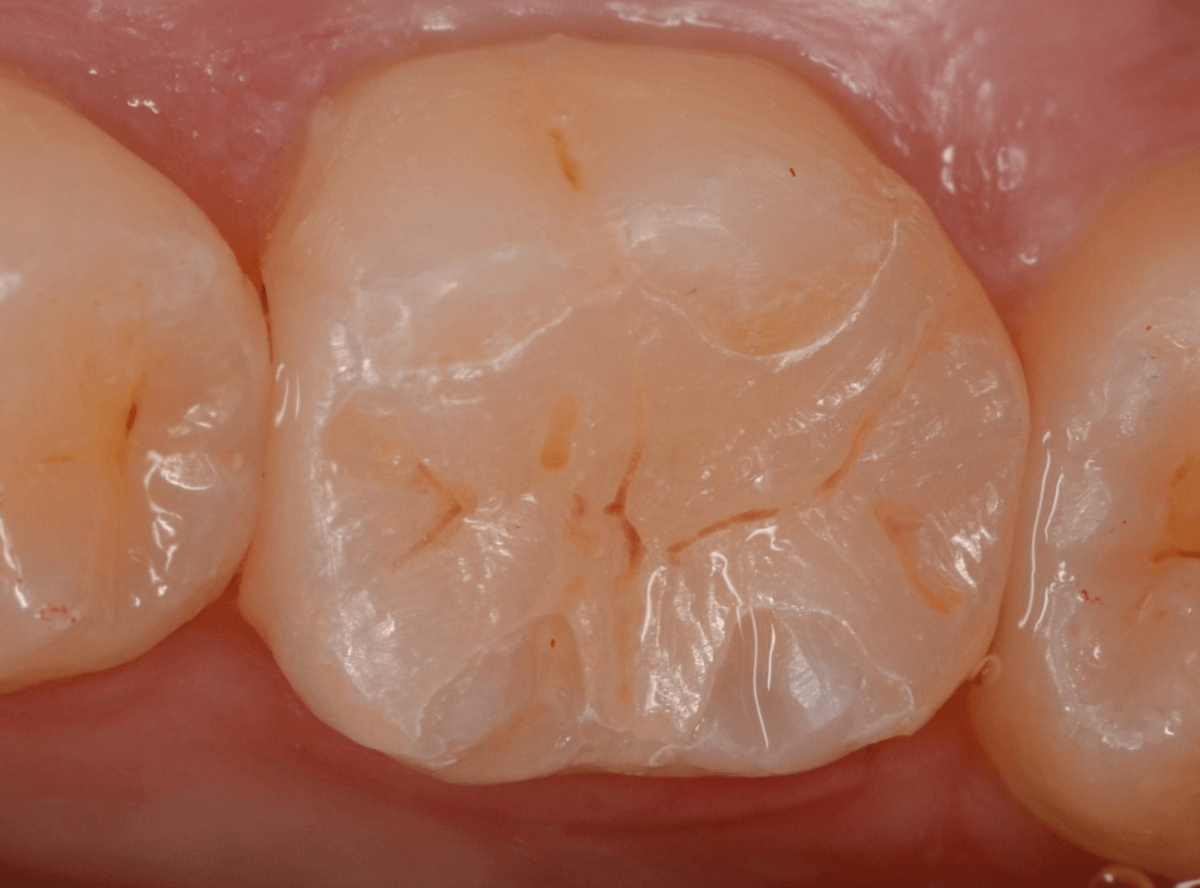

治療後の状態です。

ジルコニア・インレーはE-MAX・インレーより審美性に劣るのですが、患者さんにもご満足いただける仕上がりになり、ホッとしました。